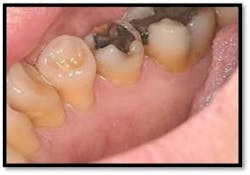

Tissue is light pink, tight and firm. All pockets are 1-3mm, no BOP

LR lingual post Tx and LL lingual post

Tissue is light pink, tight and firm. Pockets 1-3mm no BOP

Charting shows that all pockets are now generalized 1-3 mm with no BOP